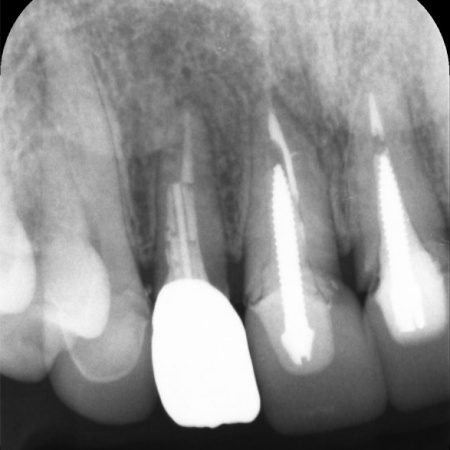

レントゲン撮影で根尖病巣の治癒を確認後、最終的な被せ物を作製するために歯の形を整えてから型取りを行います。

後日、完成したジルコニアクラウンを装着し、噛み合わせに問題がないかをしっかりと確認して、治療を終了しました。